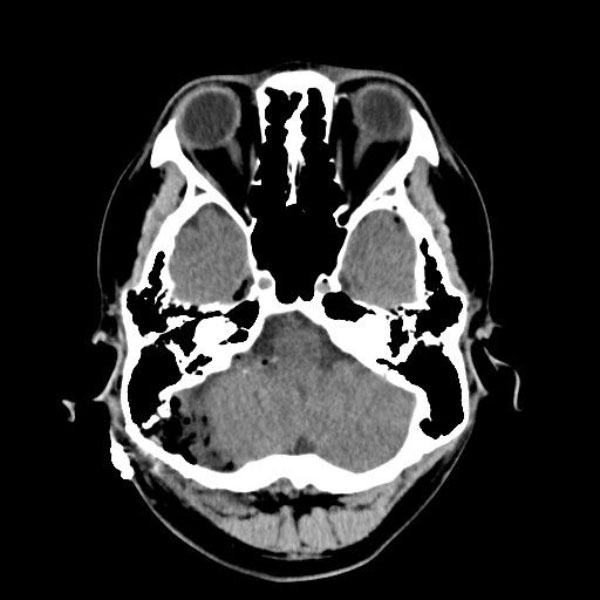

手術後

(CT)